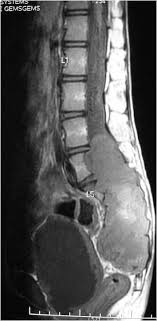

Dark Spots On Kidney Ultrasound

Dark Spots On Kidney Ultrasound. However she said i had a few things in my favor that make that unlikely. They were on either my liver or kidney and there were about 10 varrying in size.

At least â of all spots on kidneys are benign. Chronic kidney disease can also give. I am now awaiting approval for an mri.

No appendicitis but an incidental finding of a spot on my kidney. Most people don t experience any side effects. No appendicitis but an incidental finding of a spot on my kidney. However she said i had a few things in my favor that make that unlikely.